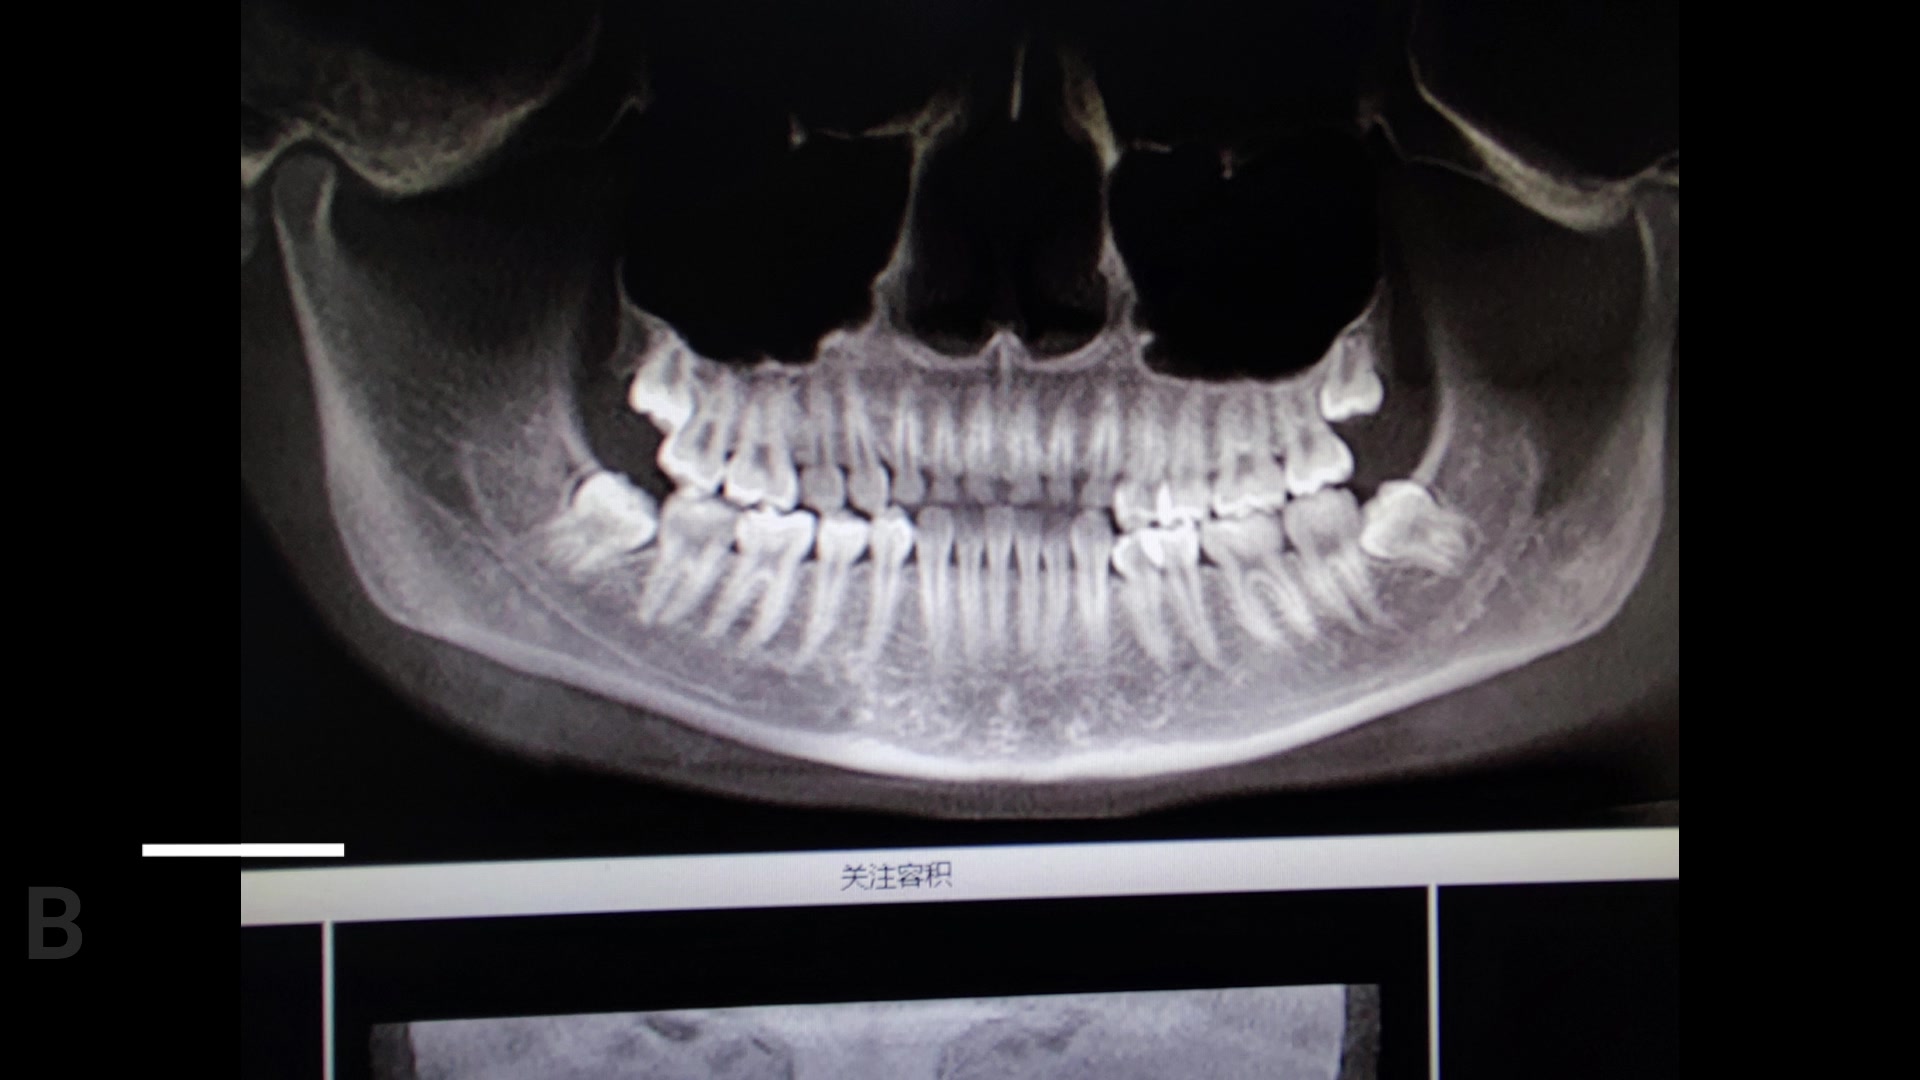

病例双侧下同时拔除(真男人就要一镜到底不剪辑)

一镜到底双侧8,倾情奉献送大家